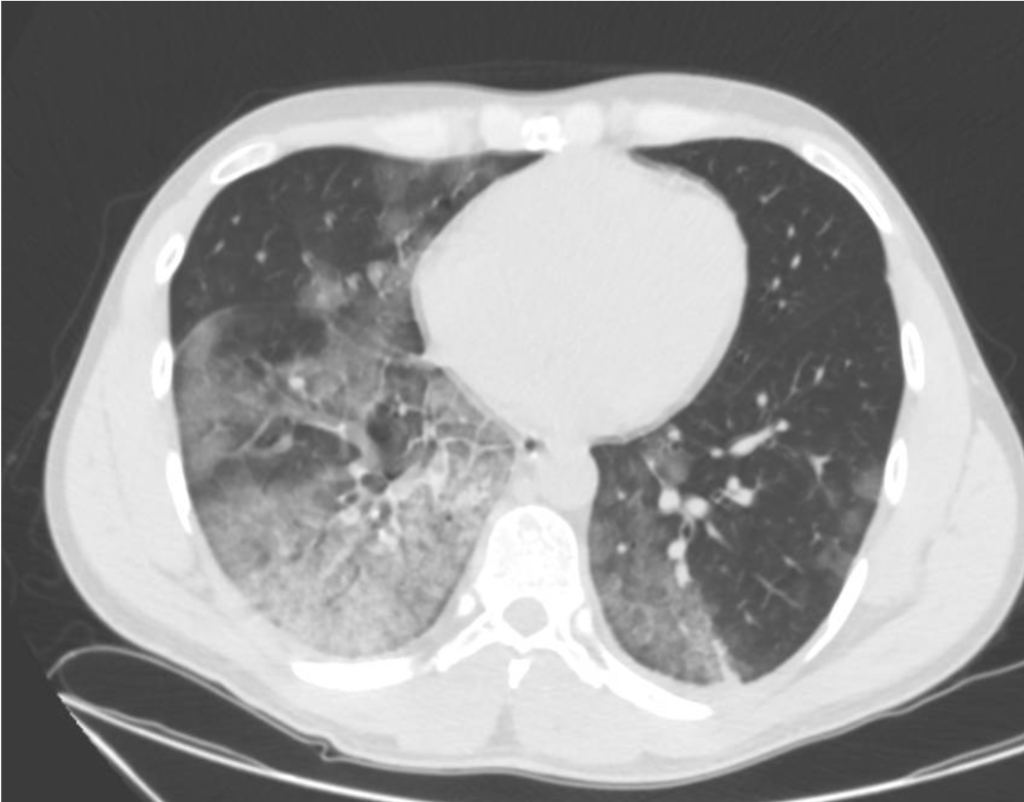

The patient tested positive for SARS-COV-2. On day 2 after admission the patient’s condition deteriorated, and he was transferred to the ICU. Another chest CT was performed. We show the ultrasound and CT images with corresponding legends (image 1-7 + video 1) and discuss the findings in relation to the diagnostic work-up of COVID-19 pneumonia.

On imaging, initial lesions are usually peripheral because SARS-COV-2 attacks the small distal airways. Several reports have described the findings in chest CT. Most commonly few, small, segmental ground glass opacities are seen peripherally and basal. These may deteriorate to become bilateral and multisegmental and finally consolidation and/or ARDS. Most common LUS signs are: vertical pleurogenic artifacts with varying degree of intensity (from few to confluent). These alternate with clear demarcation to A-lines in the same area, especially in the mid- and upper lung. Pleural thickening, sometimes marked, due to the presence of numerous, small subpleural consolidations. Lobar or translobar consolidations of large size and minimal pleural effusions. The LUS features match with the site and kind on CT.